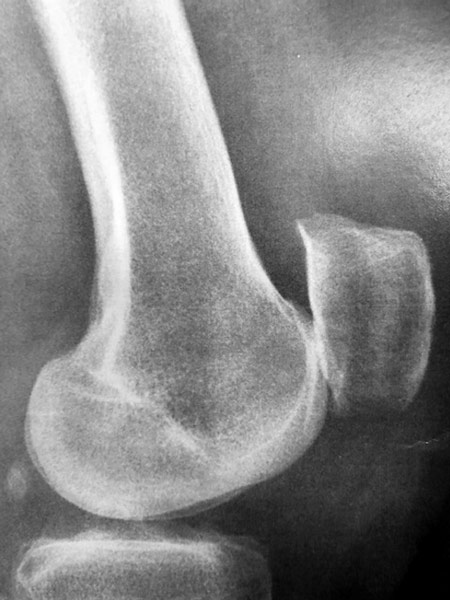

Sur ces radios de face, il n’y a pas de pincement donc pas d’arthrose au genou droit; il y a un pincement entre le fémur et le tibia au genou gauche.

Indication d’ostéotomie pour ré-axer le genou.

On réalise une ostéotomie tibiale car la déformation est localisée sur le tibia, avec une plaque interne.